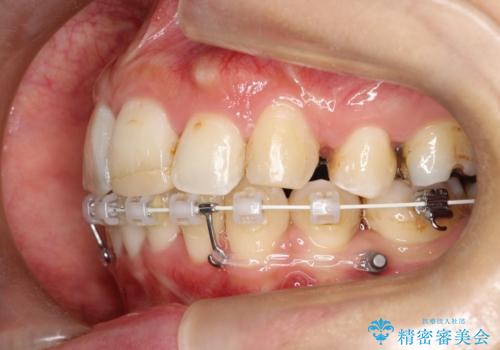

- 口元が出ていることを気にされて来院されました。精密な検査の結果、歯列全体のスペースが不足していることが判明。患者様のご希望である「口元を下げたい」というご要望を叶えるため、上下左右の小臼歯を抜歯し、そのスペースを利用して前歯を奥へ移動させる治療計画を立案しました。また、仕事上、目立つ矯正装置を避けたいというご希望から、上顎に裏側矯正、下顎に表側矯正を組み合わせたハーフリンガル矯正を提案しました。

今回の矯正治療では、口元を大きく下げるため、上下左右の小臼歯を抜歯しました。装置には、上顎は歯の裏側に装着する裏側矯正(舌側矯正)を、下顎は透明で目立ちにくい審美ブラケットを使用するハーフリンガル矯正を選択。これにより、治療中も他人の目を気にすることなく、ストレスなく過ごしていただけました。抜歯によってできたスペースを有効活用し、歯列全体を後方へ移動させることで、口元の突出感を解消。治療の結果、口元がすっきりと整い、自信のある美しい横顔を獲得していただけました。